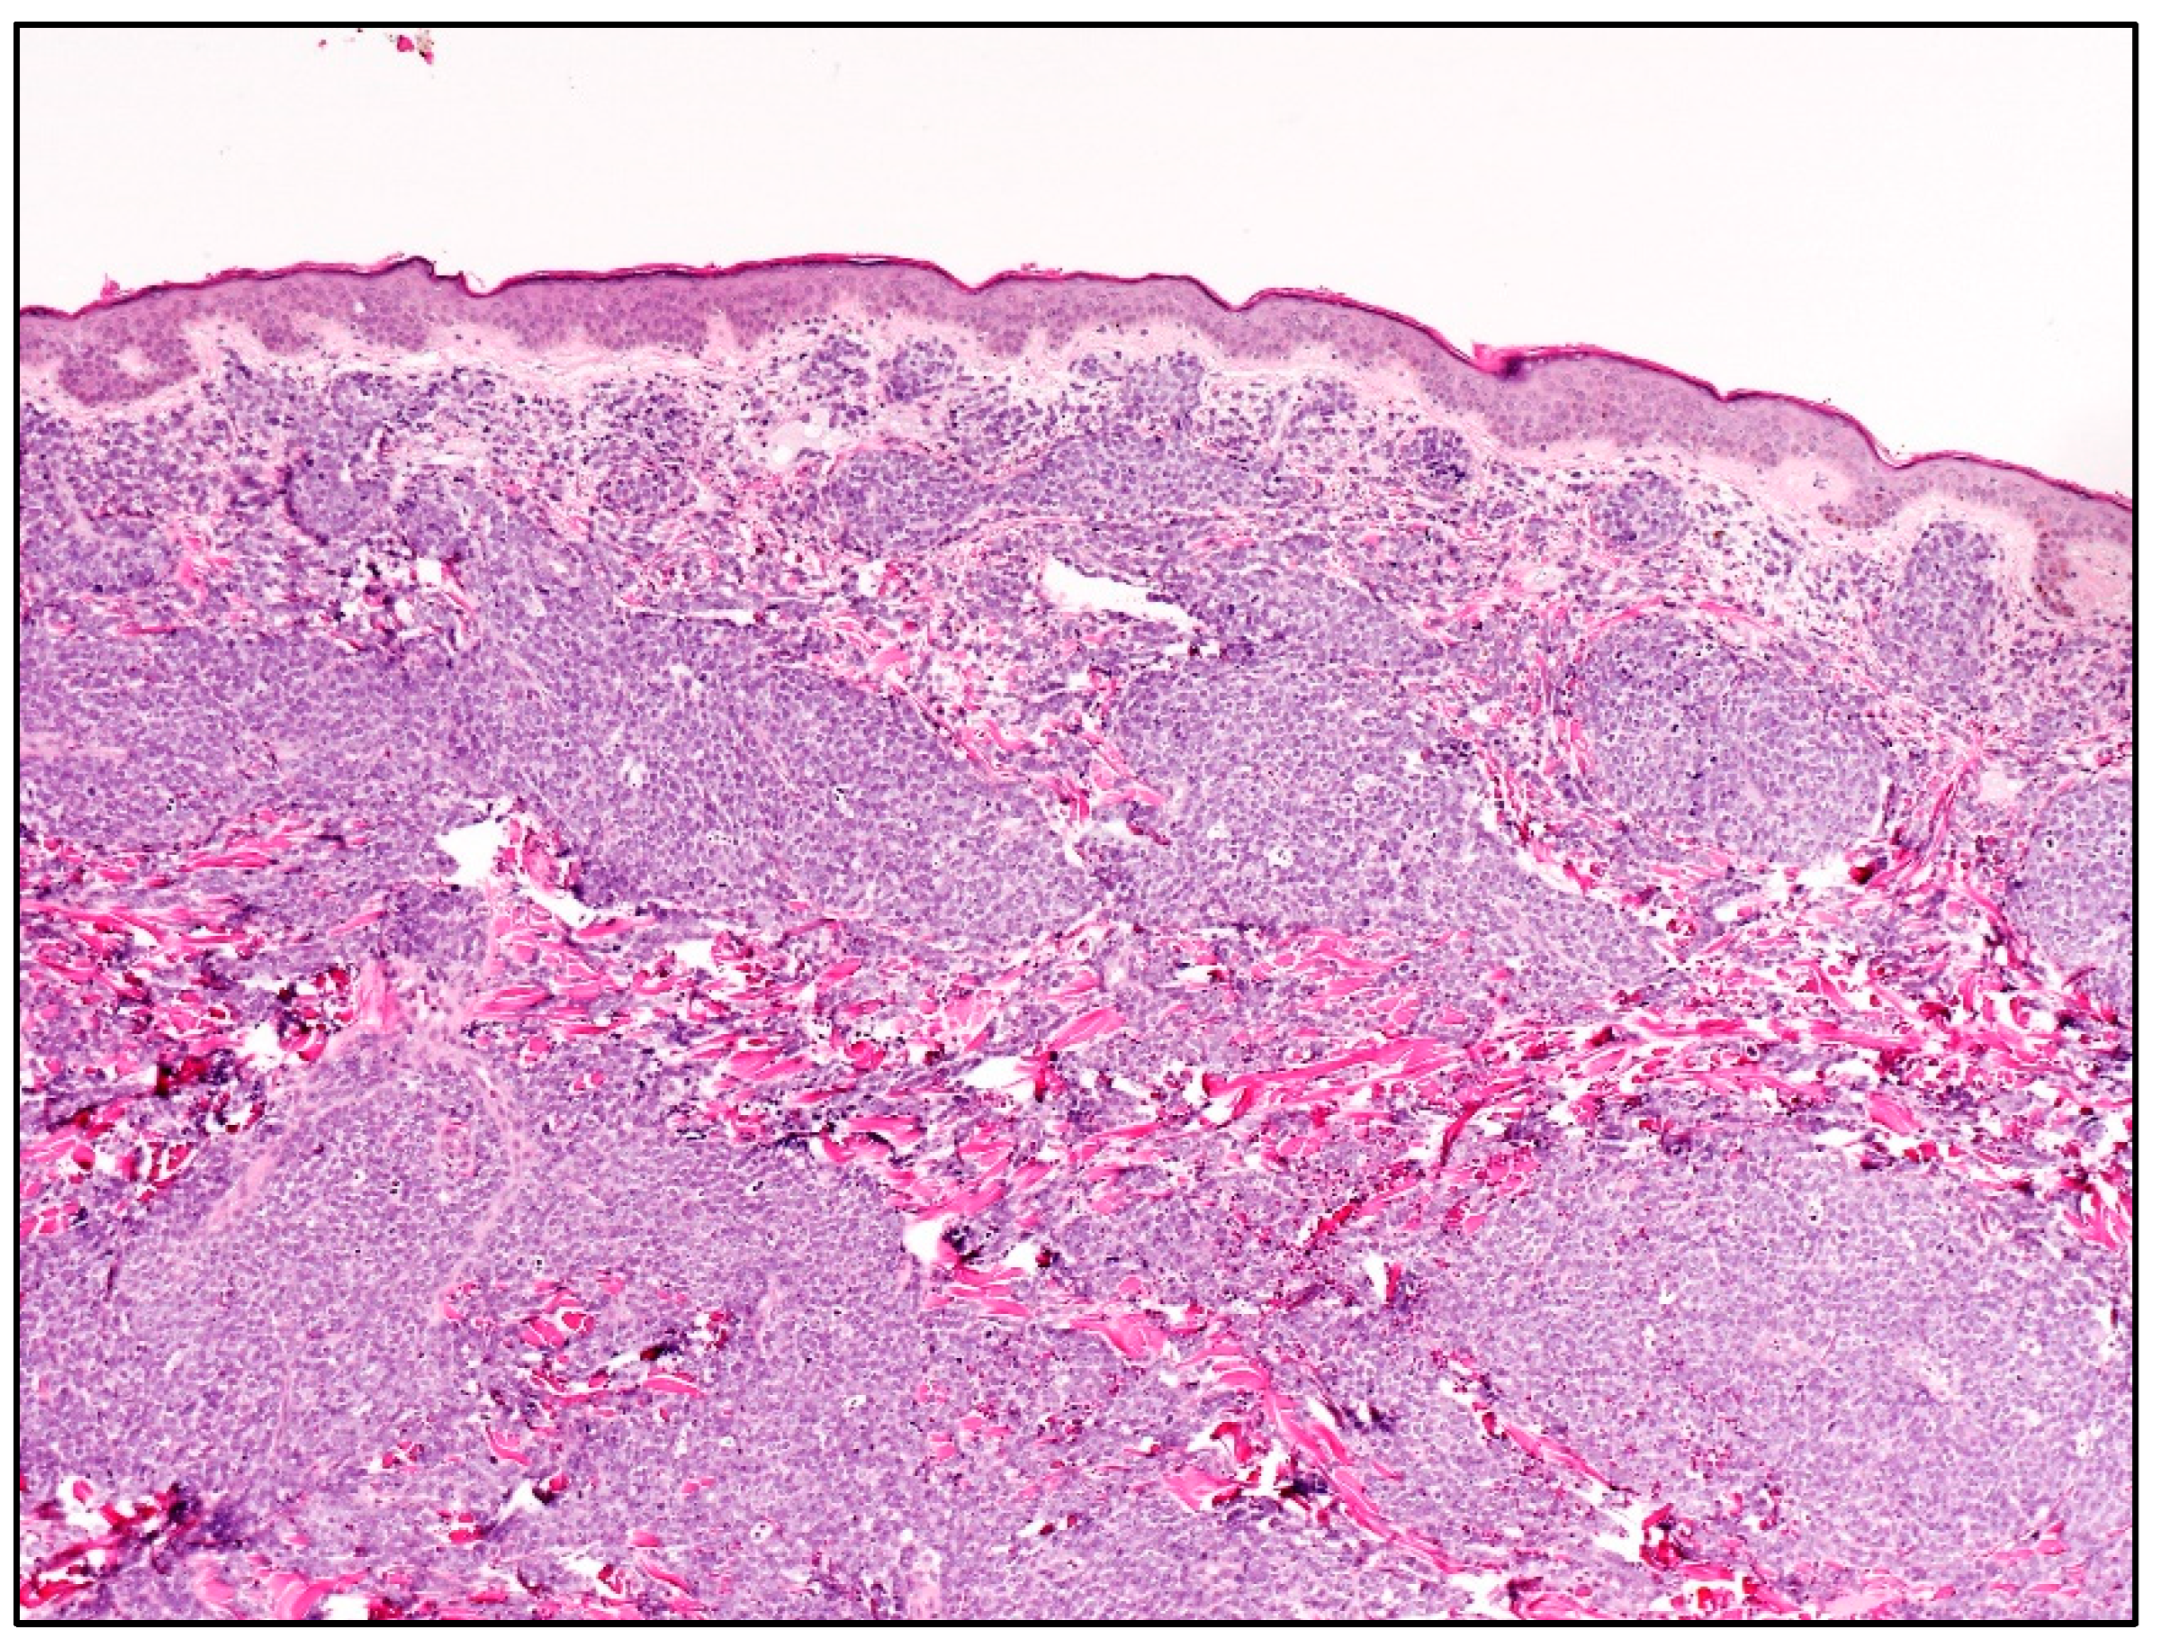

| Blastoid MCL | M:F = 3:1; late sixties | Solitary/multiple papules or nodules; often on extremities. Often previous history of MCL; skin lesions in recurrent and progressive disease | Diffuse dermal and subcutaneous tissue infiltrate; no epidermis and Grenz zone involvement. Monomorphic, medium-sized cells, round/oval nuclei, dispersed chromatin, inconspicuous nucleolus | Mature, naïve B-lymphocytes | CD20+, cyclin D1+, TdT−, CD3−, CD5+ (CD5 loss in 25-28% of blastoid MCL); aberrant expression of CD10, BCL6, CD23; TP53 overexpressed; high Ki67 | Poor. Intensive CT and immunotherapy plus ASCT; recently, anti CD19 CART cells, venetoclax, ibrutinib, acalabrutinib |

| B-LBL | F:M = 2:1 children young adults | Often solitary, firm papule or nodule on head and neck. Skin lesions in 15-33% of B-LBL; skin lesions associated with systemic disease | Dense dermal infiltrate; no epidermis and Grenz zone involvement; uniform, small, medium-sized cells, round/oval/convoluted nuclei, fine chromatin, barely visible nucleoli, scarce basophilic cytoplasm; numerous mitoses | Precursor B- lymphocytes | TdT+, CD34+, CD10+, PAX5+, cCD79alpha+, CD19+, CD22+, high Ki67 | Good prognosis in 70% of cases with B-lineage ALL-type. Multiagent CT. |

| T-LBL | M:F = 3:1 children young adults | Multiple papules or nodules on head and neck (83.3%); different anatomic areas in 41.7%. Skin lesions rare in T-LBL (4.3% of cases); skin lesions secondary to T-LBL in mediastinum or lymph nodes | Histology identical to B-LBL | Precursor T-lymphocytes | TdT+, CD34+, CD1a+, CD99+, CD117+, cCD3+, sCD3+, CD2+, CD5+, CD7+, aberrant cCD79alpha+, aberrant myeloid markers+ | Cutaneous T-LBL are rare, but with a worse outcome compared to cutaneous B-LBL despite multiagent CT. |